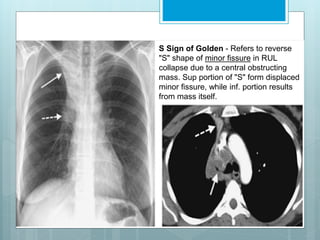

S Sign of Golden - Refers to reverse

"S" shape of minor fissure in RUL

collapse due to a central obstructing

mass. Sup portion of "S" form displaced

minor fissure, while inf. portion results

from mass itself.